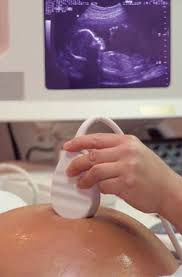

தாய் வயிற்றில் இருக்கும் குழந்தையின் பாலினத்தை 1 1/2 மாதத்திலேயே கண்டு பிடித்து விடலாம்

தாய் வயிற்றில் இருக்கும் குழ ந்தை ஆணா? பெண்ணா? என் பதை கண்டுபிடிக்க அலட்ரா சவுண்ட் ஸ்கேன் கருவி பயன் படுத்தப்படுகிறது. இதன் மூல ம் கருவுற்று 4 1/2 மாதத்துக்கு பிறகே ஆணா, பெண்ணா என் பதை கண்டுபிடிக்க முடியும்.

ஆனால் இப்போது புதிய முறை யை பயன்படுத்தி கருவுற்ற 1 1/2  மாதத்திலேயே குழந்தையின் பாலினத்தை கண்டு பிடி த்து விடலாம் என்று அமெரிக்க மருத்துவ ஆய் வாளர்கள் தெரிவித்துள்ள னர்.

தாயின் ரத்த மாதிரியை எடுத்து அதில் உள்ள மர பணு மூலம் (டி.என்.ஏ.) 1 1/2 மாதத்தில் குழந்தை ஆணா? பெண் ணா? என்பதை தெரிந்து கொள்ளலாம் என்று அவர்கள் கூறு கின்றனர்.

இதுதொடர்பாக அவர்கள் 57 விதமான ஆய்வுகளை நடத்தி யுள்ளனர். 6500 கருவு ற்ற பெண்களை இதற் காக அவர்கள் பயன்ப டுத்தி உள்ளனர். இதில் 1 1/2 மாதத்திலேயே 99 சதவீதம் சரியாக குழந் தைகளின் பாலினத்தை கண்டுபிடித்து இருக்கிறா ர்கள்.

இதன் மூலம் ஆரம்பத்தி லேயே குழந்தை ஆணா, பெண்ணா என்பதை கண்டு பிடித்து தாய்க்கு தேவையான சிகிச்சை களை அளிக்க முடியும் என்று அவர்கள் தெரிவிக்கின்றனர்.